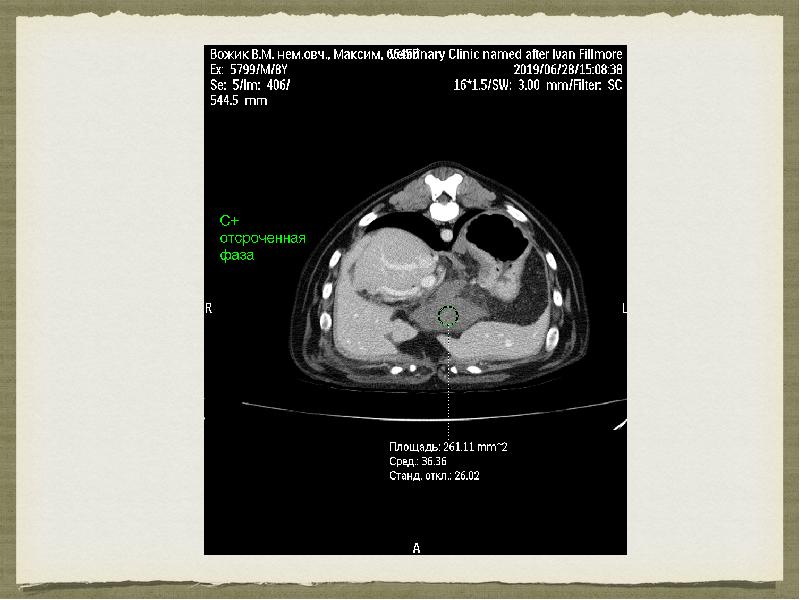

- 11. Компьютерная томография